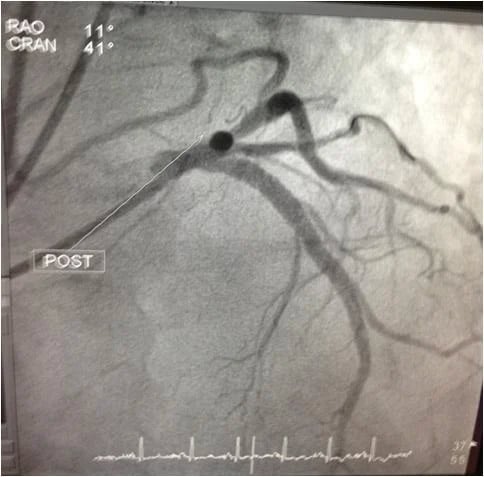

After careful proactive and preventative steps were taken, a 4.0mm x 18mm XIENCE Xpedition Stent was placed in the Ostial and Proximal LAD with optimal sizing guided by the TVC imaging system.

The after picture shows the artery is once again fully clear of any blockage.